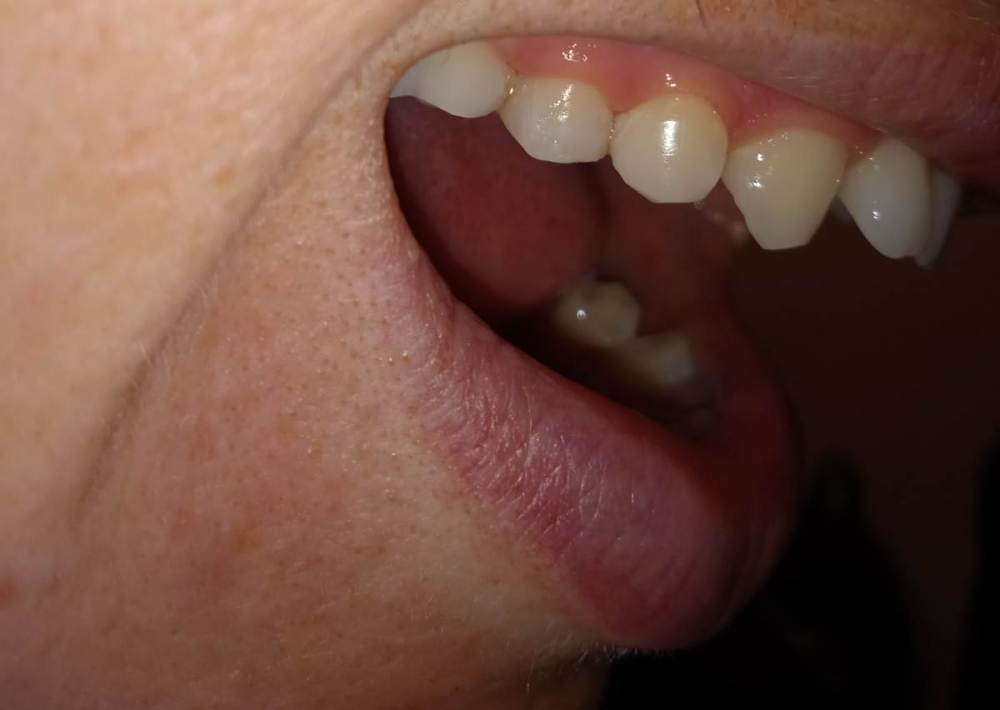

Александра117 Опубликовано 19 ноября, 2022 Поделиться Опубликовано 19 ноября, 2022 Всем Привет! Месяц назад лечила зуб верхнюю 5ку. Депульпировали и Пломбировали каналы гуттаперчей. На момент лечения в зубе уже была боль. Был поставлен диагноз пульпит. Но прошел уже месяц и боль в зубе сохраняется , при этом почти точно такая же как и до лечения. Боль постоянная ноющая средней интенсивности. Я думала это первое время после лечения такая боль будет. Но месяц прошел, а боль не уходит. Немного предыстории этого зуба: Зуб этот меня вообще не беспокоил изначально. Я пришла 12.09.2022 на прием, чтобы вылечить кариес. Стоматолог рассверлил и запломбировал. Но сказал, что очень глубокий кариес был, но решил пока сохранить пульпу и наблюдать. После лечения появились боли в зубе ,но терпимые. Через две недели боли усилились. Я пришла на прием снова с этим вопросом. Врач сказал, что после лечения глубокого кариеса могут быть боли, надо ещё понаблюдать. Ещё через пару неделю боль не проходила. Была довольно сильной. Врач принял решение депульпировать зуб. Лечение я проходила под микроскопом у опытного эндодонтиста. Именно у него я уже до этого лечила каналы у нескольких других зубов, и все было нормально. Но также это в в первый раз такое случилось, что боли такие сохраняются в течение месяца после лечения. После лечения врач сказал, что зуб меня беспокоить не должен больше. Сказал, что было лечение неосложненного пульпита. Но он беспокоит вот уже месяц. Вообще это у меня впервые, чтобы была боль в зубе и на момент лечения и после лечения каналов. До этого до болей в зубе дело не доходило. Пролечивалось раньше. Сделала свежие снимки Рентен через месяц после Лечения, их прилагаю сюда. По снимку видно, что каналы пройдены полностью до конца. Материал за Пределы Корня не выведен. Найдены все каналы. Их у меня в верхних пятерках их по два. Как и видно по КТ. Скажите, что это может быть? И что Можно сделать? Требует ли эта ситуация какого то срочного вмешательства или можно ещё наблюдать? Может ли это быть периодонтит, при том что на снимке в прикорневых тканях все спокойно? Ещё на внешней стороне зуба есть две белые трещины. Как раз на границе пломбы и стенки Зуба. В этом месте если трогать языком очень шершавая поверхность. Также, можете сказать, эти трещины это трещины Эмали или может быть что и более глубокие Трещины? ( Фото трещин тоже прилагаю) Ссылка на комментарий